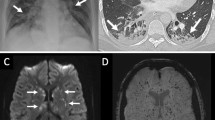

Radiological evaluation showed that the initial chest X-rays were normal in 21% of cases (data not shown), although they were abnormal in all the cases as ACS evolved in this group. Pleural effusions were seen in 76 (82.6%) of the cases on their chest X-ray and in 49 (53.3%) on their CT scan. Among these 76 cases, 12 (15.8%) had moderately severe effusions, while 64 (84.2%) had mild effusions. Multilobar atelectasis was observed in 60.8% and 90.2% of the cases on plain chest X-rays and CT scans, respectively. Not all patients had CT scans, as it is generally only requested in the most severe cases, which may explain the discrepancies in the findings between the two modalities.